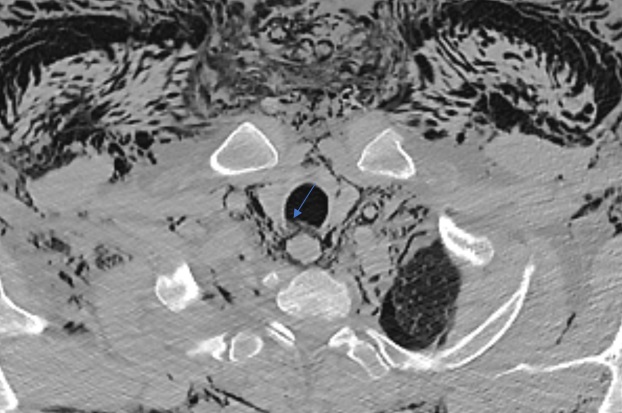

Las causas extratorácicas de neumomediastino son: fractura de senos paranasales o iatrogénicas. Además, puede producirse una disección de aire hacia el mediastino desde el espacio retroperitoneal tras la perforación de una víscera hueca.

Extrathoracic causes of pneumomediastinum include paranasal sinus fracture or iatrogenic causes. Additionally, air dissection into the mediastinum from the retroperitoneal space can occur after perforation of a hollow viscus.